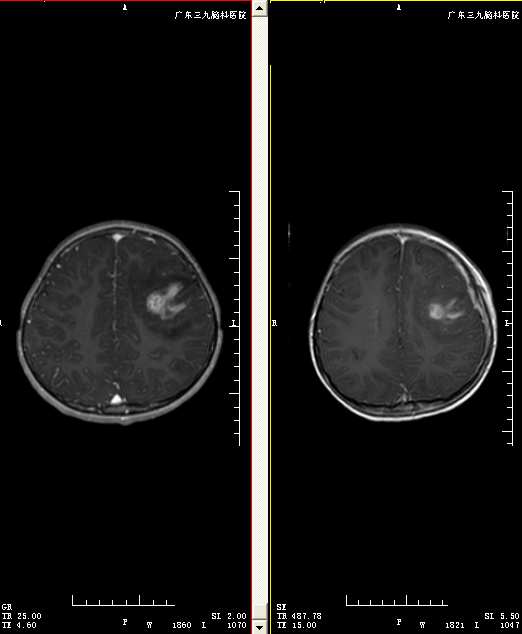

患儿刘某,男,9岁,无明显诱因下出现头痛伴四肢抽搐,以右侧肢体为主,遂到当地医院就诊,查头颅MRI显示:左侧额叶占位性病变,局部水肿明显。血液检查提示:裂头蚴阳性。为求进一步治疗,来我院就诊。

入院后完善相关检查,头颅MRI增强导航,DWI+WRS检查,行左侧额顶叶深部寄生虫取出+ICP探头置入术,手术神经外二科主任林涛主刀完成,病灶位于额顶叶深部,切除病变过程中可见一白色丝状虫体,可拉伸,缓慢拔除整条虫体,术后止血,预防癫痫,神经营养及补液等治疗,术后病理提示裂头蚴感染。经系统康复治疗后,患者康复出院,神志清楚,正确对答及遵嘱活动,对光反射灵敏,四肢肢力5级,生理反射存在,病理征阴性。电话回访,目前情况良好。